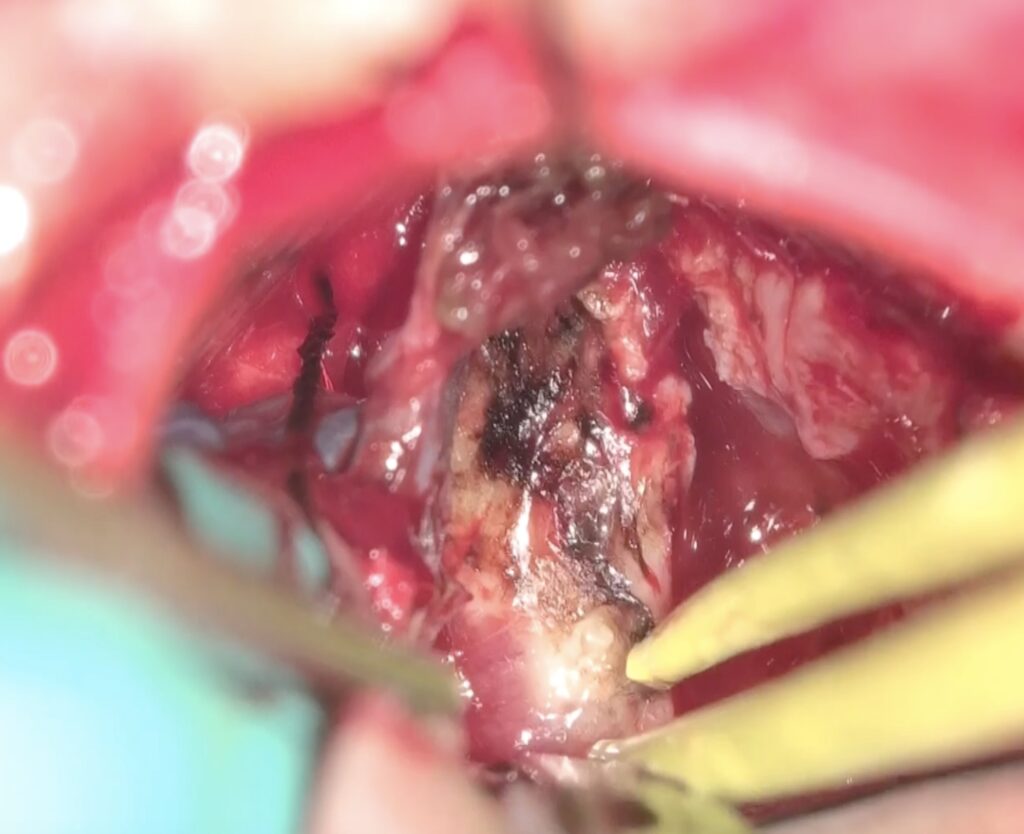

手術は通常通り行われ、顔面神経の麻痺を起こさずに摘出は終了し、うまくいったと考えていました。しかし術後より覚醒障害が続き、強い小脳腫脹を生じたため、術後脳室ドレナージ術、バルビタール麻酔療法、気管切開まで行い急性期を乗り切りました。術前より下肢静脈血栓症を合併していたことと、Petrosal veinが通常より広範囲の静脈環流を行っていたためと考えられます。現在、覚醒し、四肢が動くようになってきました。

手術は通常通り行われ、顔面神経の麻痺を起こさずに摘出は終了し、うまくいったと考えていました。しかし術後より覚醒障害が続き、強い小脳腫脹を生じたため、術後脳室ドレナージ術、バルビタール麻酔療法、気管切開まで行い急性期を乗り切りました。術前より下肢静脈血栓症を合併していたことと、Petrosal veinが通常より広範囲の静脈環流を行っていたためと考えられます。現在、覚醒し、四肢が動くようになってきました。